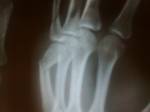

22042012353.jpg

з/перелом V кистной кости левой кисти со смещениемПросмотров: 2673Комментариев: 8 Mr.Freeride